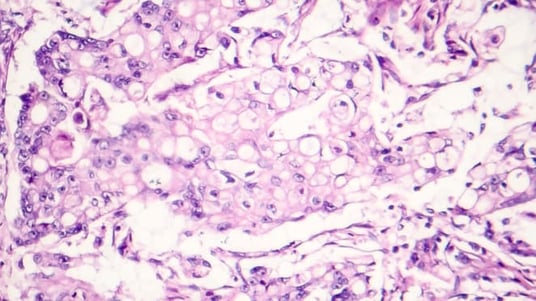

SMAB10 staining in human tumor TMAs was binned into four classes based on semi-quantitative immunohistochemical intensity scoring (negative or grade 1-3). This scoring assessment was performed by visual inspection by one of Precision for Medicine’s board-certified pathologists. This analysis confirmed that SMOX is expressed more frequently in multiple cancers compared to non-diseased tissues, with the greatest intensity and highest frequency of positive hSMOX staining in colon cancer tissue. Positive tumor staining was also visible in breast and prostate cancer tissue and was least frequent and intense in lung cancer tissues.

(A) hSMOX staining on human tumor TMAs using a SMAB10 IHC assay. (B). Grading of hSMOX staining frequency in human tumor TMAs.